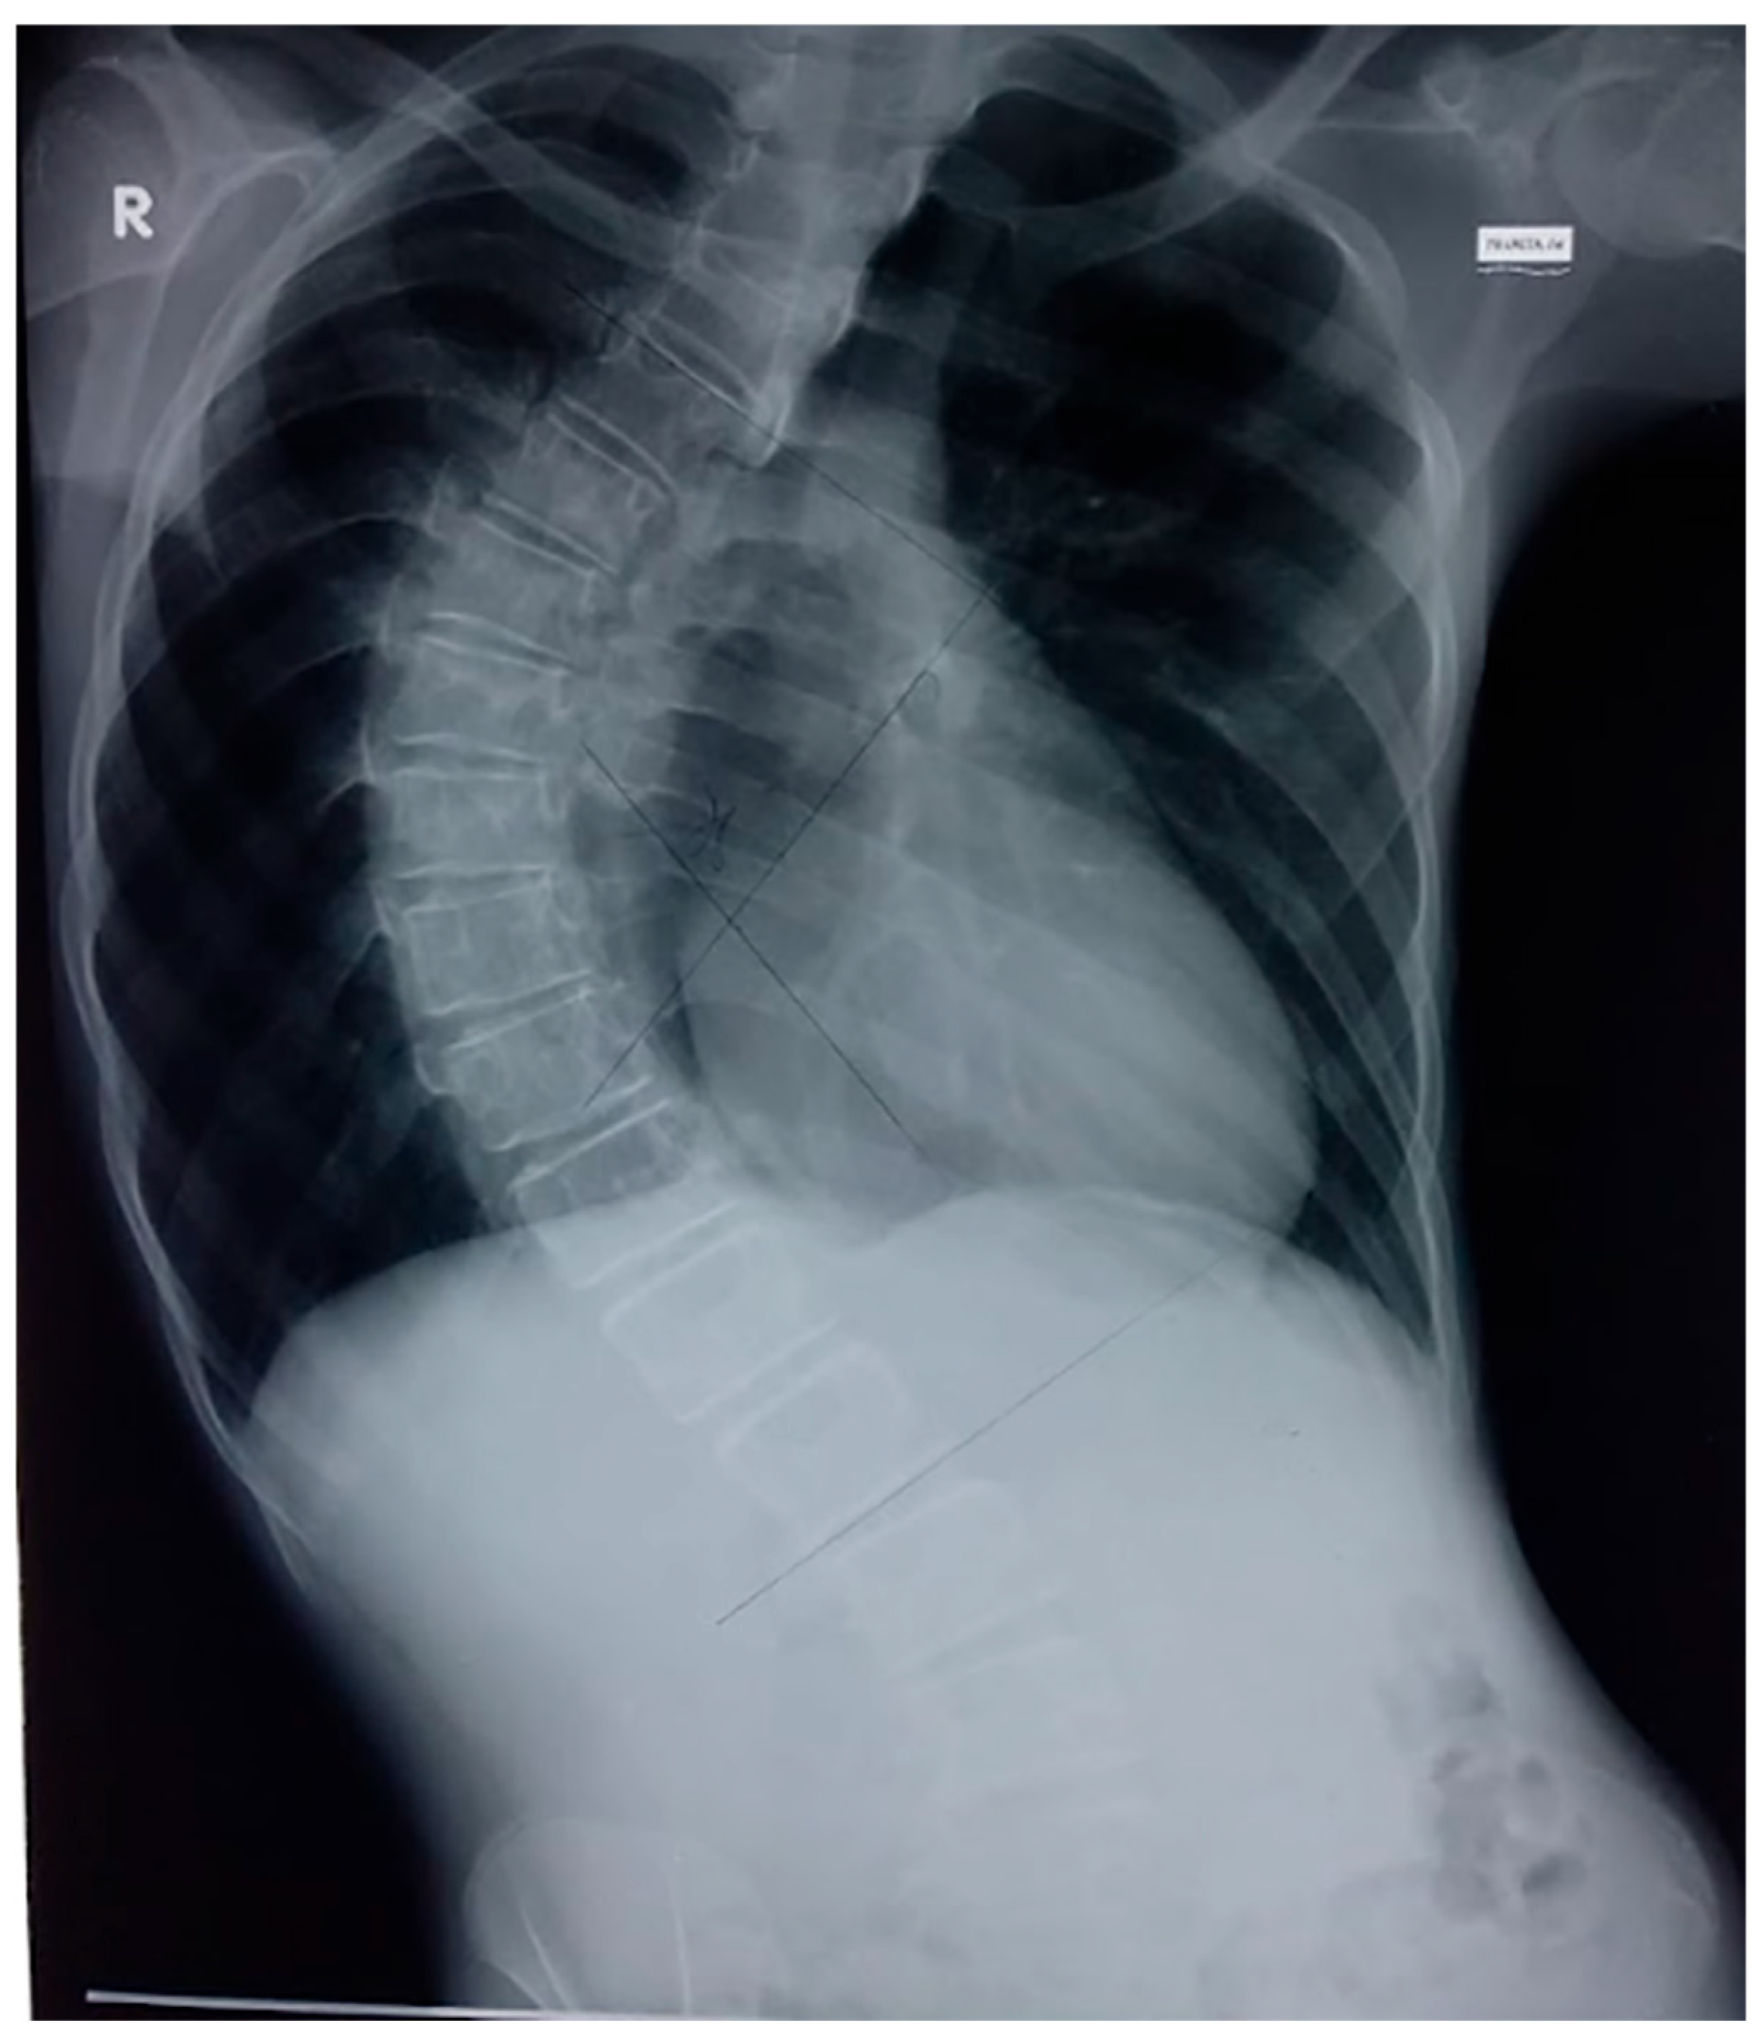

The patient presented with multiple comorbidities, including heart failure with preserved ejection fraction (HFpEF) secondary to myocardial hemosiderosis, diabetes mellitus due to pancreatic hemosiderosis, which was well controlled with insulin, and osteoporosis. The patient was also diagnosed with thoracolumbar scoliosis in 2018, as seen from his chest X-ray projection taken in 2019 (Figure 1). These findings were compounded by the patient’s low BMI, suggesting underweight status.

Figure 1.

The patient’s chest X-ray with a posteroanterior (PA) projection (2019) depicting an illustration of thoracic scoliosis with a rightward curvature that may be seen in a patient with thoracolumbar scoliosis (R indicates the right side).